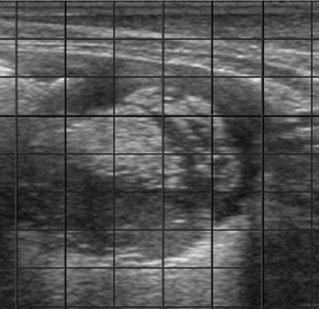

Puntuación 3

Patrón de consolidación pulmonar: masa de aspecto hipoecoico, parecido a la imagen ecográfica del hígado, como consecuencia de la inflamación y depósito de exudados en el parénquima pulmonar (1 o más lesiones lobulares de 1-6 cm2).

Derrame pleural: presencia de líquido que separa la pleura parietal de la visceral con cantidad variable de hebras ecoicas correspondientes con la presencia de fibrina.

Puntuación 4

Consolidación pulmonar: masa de aspecto hipoecoico, parecido a la imagen ecográfica del hígado, como consecuencia de la inflamación y depósito de exudados en el parénquima pulmonar (1 o más lesiones lobares de >6 cm2).

Abscesos: cápsula gruesa con un contenido interior heterogéneo. Normalmente se asocia con procesos crónicos y con pronóstico reservado.